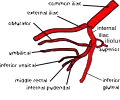

| Branches | Iliolumbar artery, lateral sacral artery, superior gluteal artery, inferior gluteal artery, middle rectal artery, uterine artery, obturator artery, inferior vesical artery, superior vesical artery, obliterated umbilical artery, internal pudendal artery, vaginal artery |

The arrangement of branches of the internal iliac artery is extremely variable.[3] Typically, the artery divides into an anterior division and a posterior division, with the posterior division giving rise to the superior gluteal, iliolumbar, and lateral sacral arteries. The rest usually arise from the anterior division. Because it is variable, an artery may not be a direct branch, but instead might arise off a direct branch.

The following are the branches of internal iliac artery: